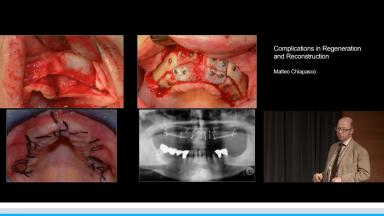

Complications in Regeneration and Reconstruction

Matteo Chiapasco

This lecture reviews in detail the various defects encountered in clinical practice that may need regenerative procedures for hard and soft tissue augmentation. The presentation is supported with excellent visual aids that illustrate how these defects can be reconstructed for prosthodontically driven implant placement. It also addresses how to prevent complications in regenerative and reconstruction procedures as well as the predominant treatment options to manage these complications. Clinical outcomes are supported by reference to several studies and clinical recommendations from the 4th ITI Consensus Conference.

• describe the various bone defects encountered in clinical practice to be considered before implant placement

• discuss how to prevent complications related to bone augmentation procedures

• discuss the predominant treatment options for management of complications associated with reconstructive procedures

• explain therapeutic interventions to manage complications at different stages of implant therapy